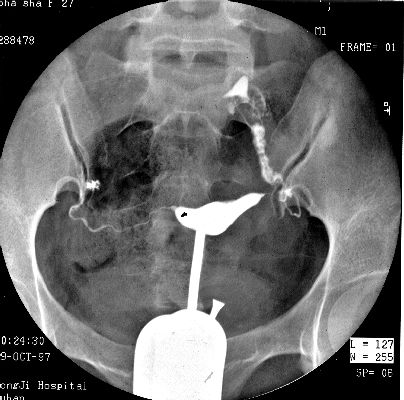

照片名称:子宫输卵管造影2

照片名称:子宫输卵管造影1

照片名称:子宫输卵管造影